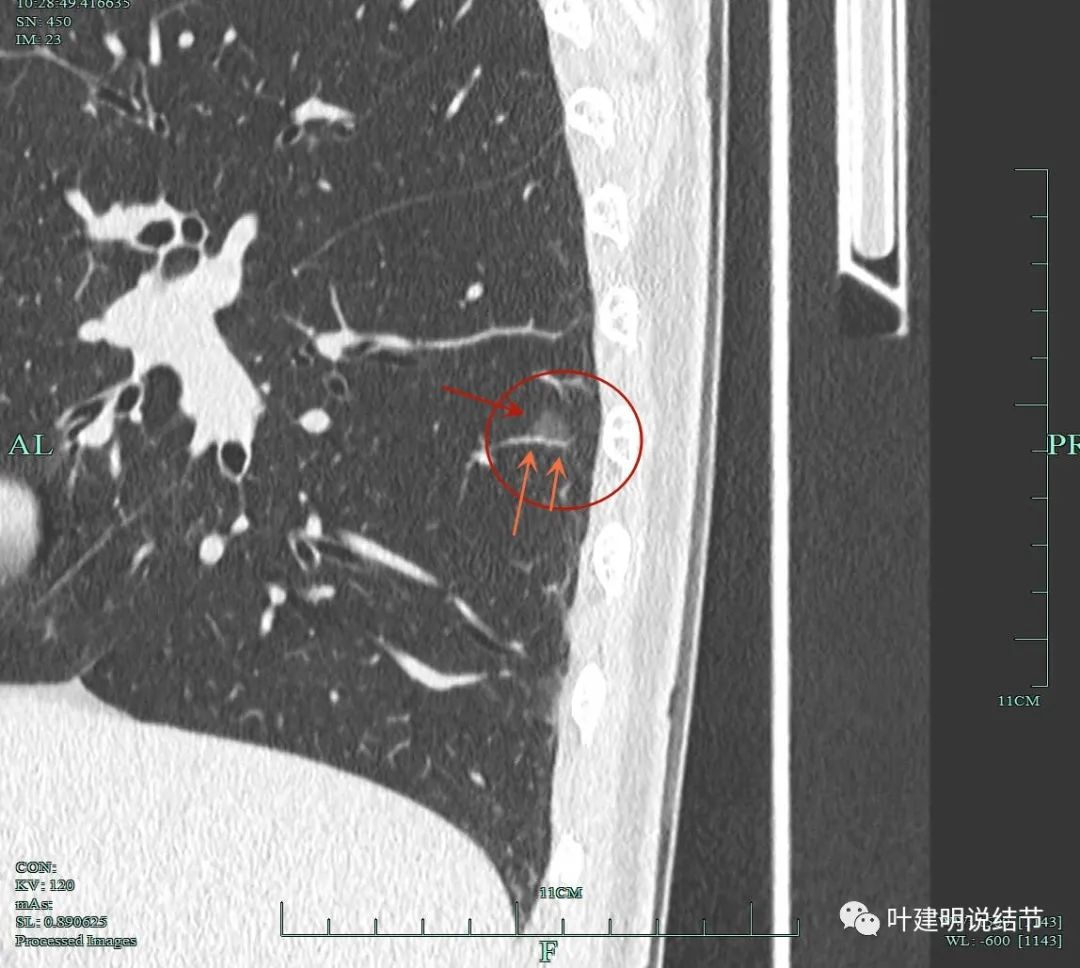

靶重建影像展示:

病灶8重建后显示血管与结节间没有间隙,而且瘤肺边界很清。

病灶9的重建发现不是实性结节,而混合磨玻璃密度。绿色箭头示边上有磨玻璃成分,而且紫色箭头示边缘是毛糙的,红色箭头示整体轮廓是清的。

上图也显示病灶边缘毛糙,不光滑,与胶原结节、淋巴结等良性结节是不符合的。